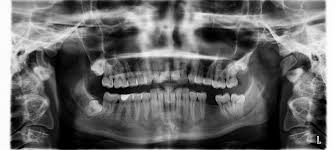

Treatment for loose teeth in adults. If there are any problems that might lead to loose teeth the dentist should be able to catch them long before any serious damage is actually done. 8 linhas Surgical treatments. Removing plaque deposits and bacteria from the surface of your teeth through deep cleaning is often an effective way of treating gum disease.

The faster you get to the dentist the better your chance of saving your tooth. How to Strengthen Loose Teeth in Adults The average dentist is likely to offer a series of antibiotics as well as loose teeth procedures that will be time consuming and expensive. Root planning and scaling.

If your loose adult tooth needs treatment there are numerous different things which your dentist might prescribe. Finally your dentist may also perform tooth splinting.

Prevention And Treatment Options For Loose Teeth In Adults C R Dental Group

If you dont destroy the disease you will not be able to stop the problems returning. Loose teeth caused by gingivitis can be partly treated with regular flossing. This is where your dentist uses an x-ray or a dental probe to examine your gums and teeth. If your loose adult tooth needs treatment there are numerous different things which your dentist might prescribe. Also known as periodontitis this. Some of the common treatments for loose teeth are flap surgery bone grafts soft tissue grafts splinting bite adjustment and other dental appliances to help support your teeth. Dental Appliances - Appliances like bite splints can help to control damages from teeth grinding and help the mouth heal after dental surgery.